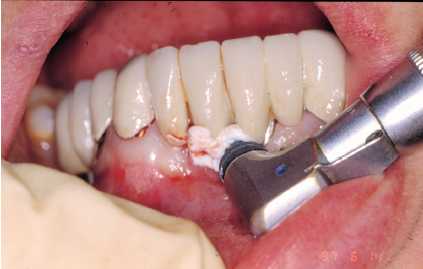

— Eliminación de placa bacteriana y/o cálculo

con curetas de plástico, oro, titanio o carbono composite

(Figura 3), puntas de ultrasonido de carbono composite (Figura

4). No se debe emplear ningún instrumento con punta

metálica, ya que se corre el riesgo de arañar

la superficie del implante y crear nichos en los que proliferen

las bacterias.

Figura 4. Tratectomía con punta de carbonocomposite